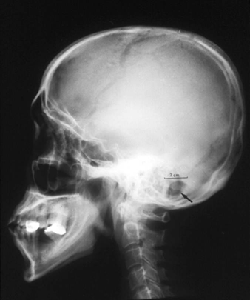

鍵穴から見える脳神経

皮膚を十分に引き、小さくも十分な手術野を確保する

約2cmの開頭(矢印部の黒く抜けたところ)